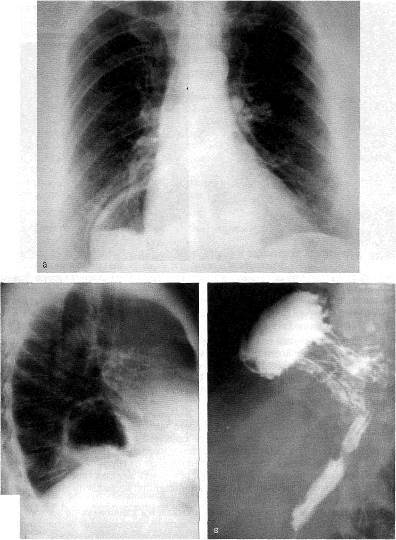

Анатомия диафрагмы и треугольника Бохдалека

Раздел: Визуальный дайджест